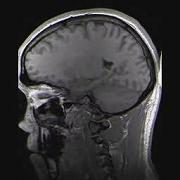

Sie sind hier: Startseite Nachrichten Ernährung Veränderungen im Gehirn von Patienten mit Essstörung erstmals im Kernspintomografen sichtbar gemacht MRT-Aufnahme eines menschlichen Kopfes in sagittaler Schnittebene Bild: Structural.gif / de.wikipedia.org

MRT-Aufnahme eines menschlichen Kopfes in sagittaler Schnittebene Bild: Structural.gif / de.wikipedia.org